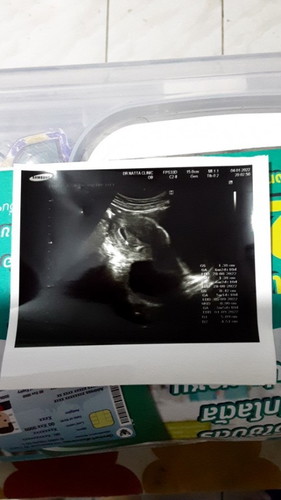

ตั้งครรภ์ได้ 6 สัปดาห์ เจอซีสที่รังไข่ 5 cm ใครพอมีประสบการณ์ช่วยแนะนำหน่อยค่ะ เริ่มคลื่นไส้ แพ้ท้อง

เจอถุงตั้งครรภ์พร้อมถุงซีสเลย

ของเราก็เป็นค่ะ เจอถุงน้ำในรังไข่ ตอนนั้นเจอ4 cm หมอบอกถ้าไม่ยุบต้องผ่าตัด แต่ตอนนี้ยุบแล้วค่ะ ไม่ได้ผ่าตัด น้องก็แข็งแรงดี ตอนนี้ 19 วิคแล้วค่ะ